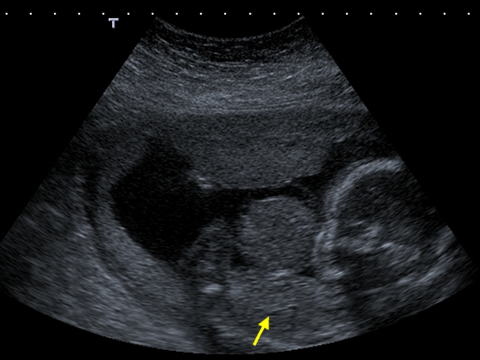

An abdominal wall defect is an abnormal type of hernia either through the cord insertion or by the side of the cord. In this ultrasound image, note the outline of the herniated contents outside the abdomen. The fetal spine and fetal stomach can also be seen.